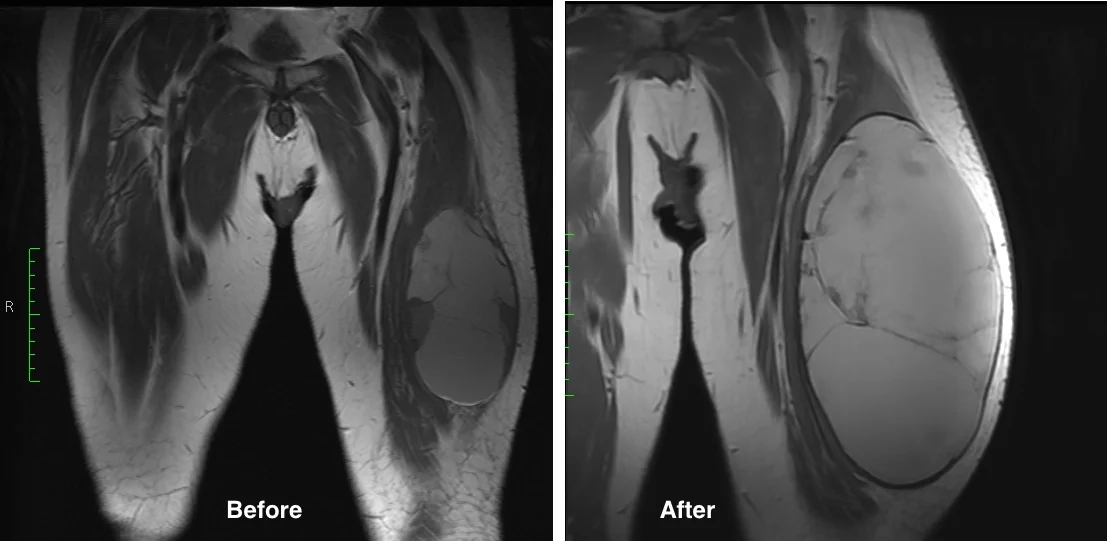

This 62 year old man presented with thigh pain and swelling. MRI imaging showed a large mass within the quadriceps muscle (vastus lateralis). Biopsy was performed at the time of initial evaluation and confirmed a high grade undifferentiated sarcoma. The tumor was localized to the thigh (Stage III).

He completed 5 weeks of preoperative radiation and then underwent surgery. Below are MRI images of his tumor. The first image below shows the change in the tumor before and after radiation. It is not uncommon for sarcomas to enlarge during radiation therapy. This is thought to be due to cell death from radiation resulting in hemorrhage

The next two images above show the extent of the tumor at the time of surgery. The last image demonstrates how most of the mass is fluid and blood, as the large bulk of the mass does not take up contrast and remains dark.